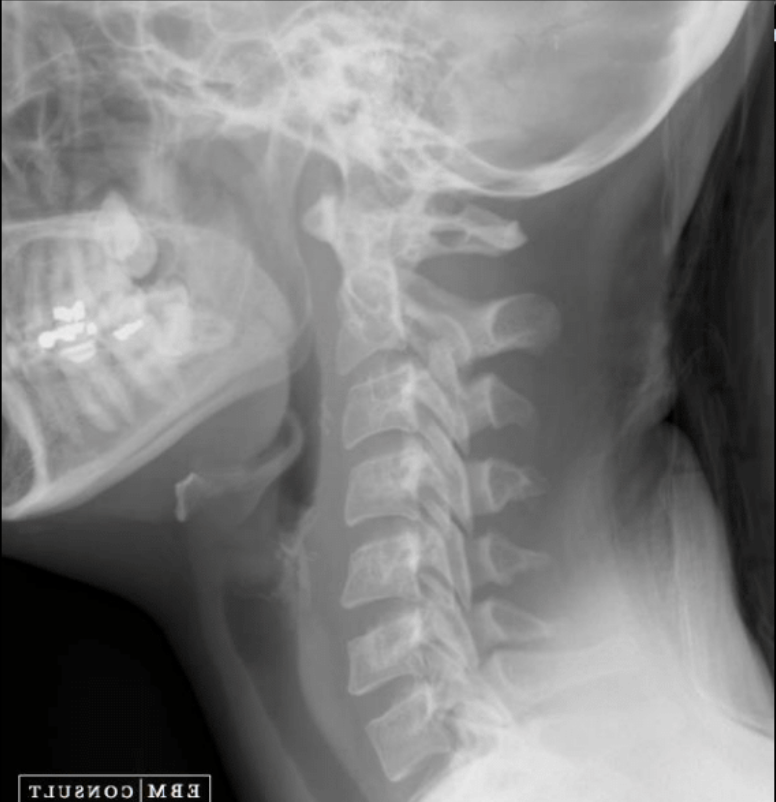

6

Q

RX y qué encontramos

A

RX lateral de cuello con técnica blanda

- Obstrucción nasofaríngea

- Engrosamiento de adenoides

9

¿Qué observas?

Oclusión nasofaringe